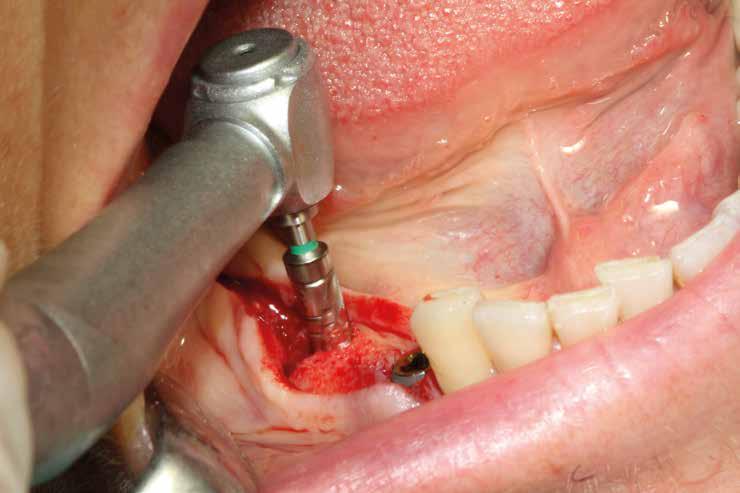

Un ridotto scollamento dei tessuti molli riduce edema e dolore post operatorio, mentre la preparazione del sito implantare a bassi giri con irrigazione limita il trauma del tessuto osseo.

Una incisione lineare netta si estende coinvolgendo minimamente il dente mesiale e maggiormente in direzione distale, consente di evitare l’esecuzione di incisioni di scarico che provocano una interruzione della vascolarizzazione maggiore, senza ridurre la visibilità del campo operatorio.

La microvibrazione degli inserti ultrasonici non presenta la tendenza allo scivolamento tipica delle frese rotanti consentendo di mantenere con maggiore semplicità e precisione l’orientamento del tunnel implantare, soprattutto quando si prepara all’interno dei un alveolo post-estrattivo agendo su una superficie liscia e inclinata. Nelle immagini è possibile vedere una serie di situazioni in cui